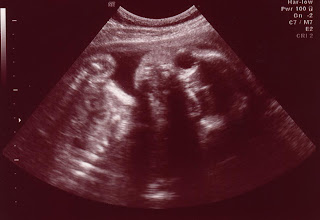

Alexandria (no middle name yet) - the newest grandchild-to-be. Chris and Matt invited me to go along for the ultrasound this morning. We got to see the heart beating (very, very cool), various bones, her spine, and bits of her cute face. Alex was being a tad uncooperative so we didn't get a really good look at her face, but the tech says she looks just like her daddy (maybe because neither has hair at the moment??)

Alex is about 2 pounds 10 ounces right now and her due date is still August 28.